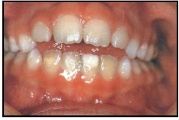

kaaries igemeäärel

kaaries